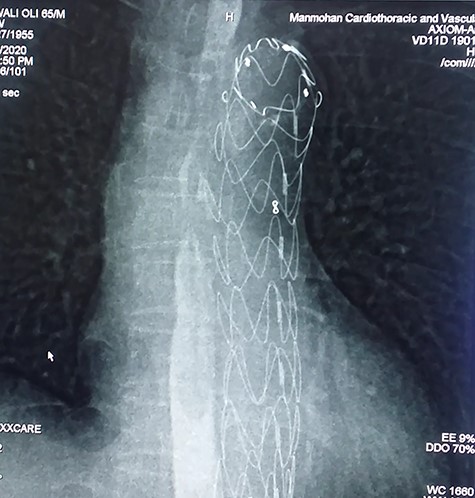

With the above findings, a diagnosis of ruptured descending thoracic aortic aneurysm with AEF was made. The patient was immediately taken for emergency TEVAR where 34 × 34 × 167-mm stent graft (Medtronic Inc. Valiant Thoracic Stent Graft) was deployed using a guidewire beyond the left subclavian artery till above the diaphragm via an incision over the left common femoral artery. Check angiogram showed no leak (Figs 4 and 5). Due to existing mediastinitis, feeding jejunostomy (FJ) was preferred over esophageal stenting. FJ was performed in the same setting after the endovascular procedure.